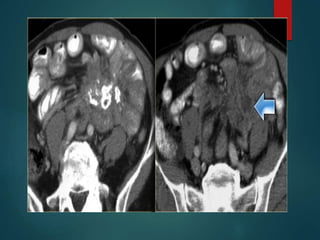

Malignant mesothelioma…

• Sheet like peritoneal thickening.

• Absence of lymphadenopathy

• Ascities is minimal

50/M

Asbestosis exposure

No primary

70/M

Vs peritoneal carcinomatosis

Diffuse mesothelioma…..